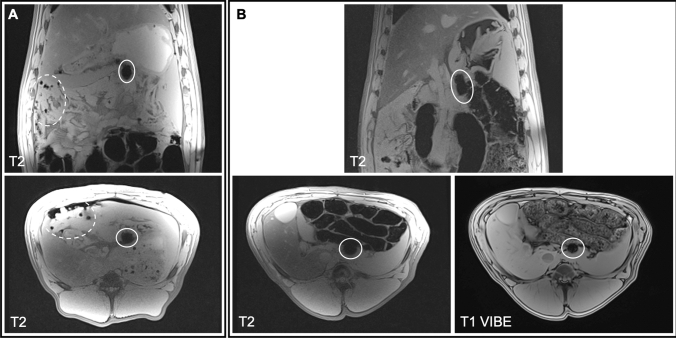

The default protocol for identifying nodes containing the FerroTrace tracer on preoperative MRI was the T2-weighted coronal plane scan. A total of 8 animals underwent MRI imaging for evaluation of preoperative LN mapping. On this scan, FerroTrace at the injection site and inside draining LNs produced very strong negative contrast and susceptibility ‘bloom’ artefact in T2-weighted MRI (Fig. 2). However, in all animals there existed some form of artefact mimicking the negative contrast of FerroTrace-positive LNs as a result of gas pockets (e.g. among the small bowel), introduced when the abdomen was insufflated for injection. Likewise, in all but 1 animal (animal 3), the large bowel—which produced endogenous negative contrast on the T2-weighted scan—was positioned in close proximity to the stomach and overlapped regions where draining LNs were anticipated to reside (Fig. 2). Fortunately, the positioning of the bowel only impacted the identification of FerroTrace-positive LNs in 1 instance (animal 5), whereby the bowel obscured the signal of a single LN on T2-weighted MRI. In this instance, positive MRI identification was instead achieved using the T1 VIBE protocol, which was able to differentiate between signals from the bowel and FerroTrace, particularly when using the shortest TE (1.33 ms) in the multi-echo series (Fig. 2). Despite this success, the T1 VIBE protocol results in a significant reduction in the characteristic signal from FerroTrace; hence the T2-weighted protocol remained the default for preoperative LN mapping.

Fig. 2.

MRI scans of swine abdomen coronal (top) and axial (bottom) planes were used to locate draining LNs (solid oval). A An example T2 scan where a magnetic LN is clearly distinguishable from air pockets (dashed oval), surrounding tissue, and large bowel. B An example where LN mapping using the T2 protocol was made difficult by LN proximity to the large bowel. In this instance the T1 VIBE protocol (1.33 ms TE) was more effective at distinguishing the SLN